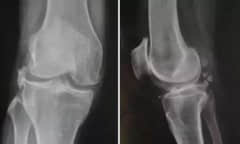

关节炎有五类,您能分清吗?